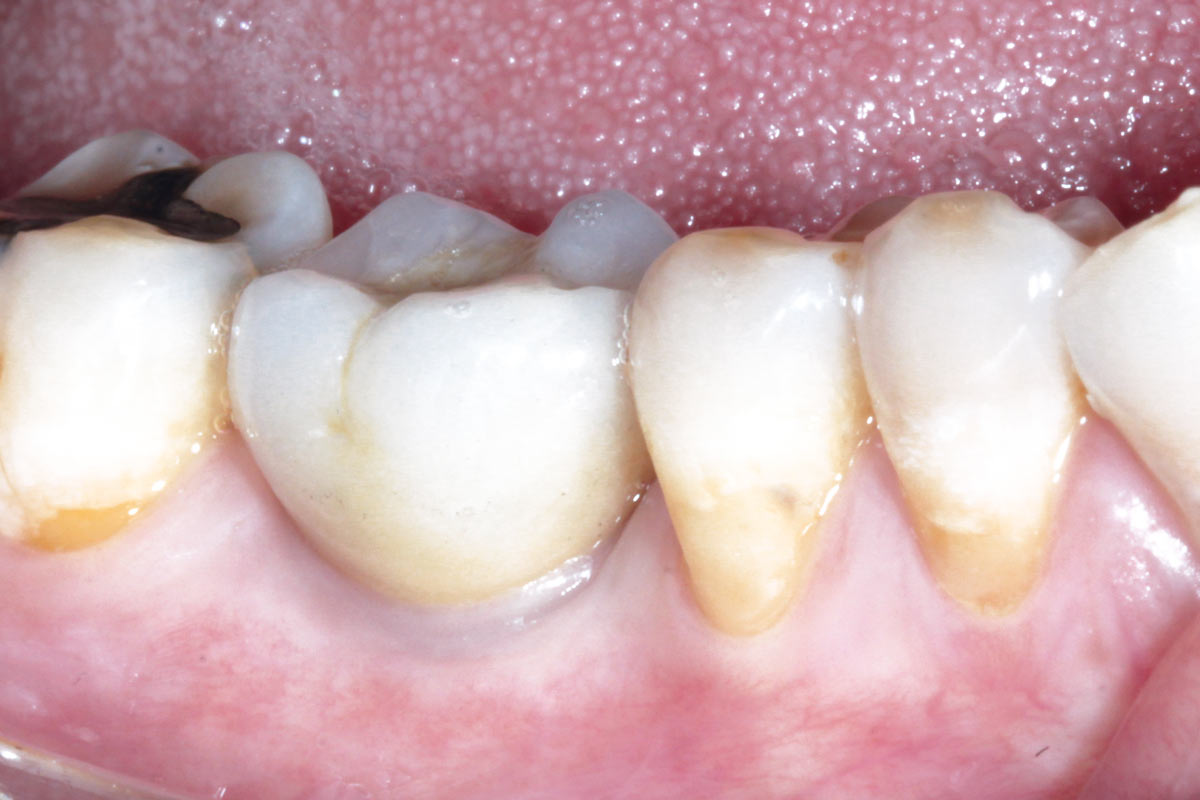

Pre-operative situation showing tooth 21 with deep periodontal pocket. Tooth presented with mobility grade III.